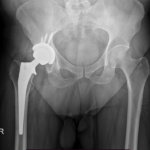

Total hip replacement (THR) is a surgical procedure in which the damaged cartilage and bone is removed from the hip joint and replaced with artificial components. The hip joint is one of the body’s largest weight-bearing joints, located between the thigh bone (femur) and the pelvis (acetabulum). It is a ball and socket joint in which the head of the femur is the ball and the pelvic acetabulum forms the socket. The joint surface is covered by smooth articular cartilage which acts as a cushion and enables smooth movements of the joint.

The surgery is performed under general anesthesia. During the procedure a surgical cut is made over the hip to expose the hip joint and the femur is dislocated from the acetabulum. The surface of the socket is cleaned and the damaged or arthritic bone is removed using a reamer. The acetabular component is inserted into the socket using screws or occasionally bone cement. A liner made of plastic, ceramic or metal is placed inside the acetabular component. The femur or thigh bone is then prepared by removing the arthritic bone using special instruments, to exactly fit the new metal femoral component. The femoral component is then inserted to the femur either by a press fit or using bone cement. Then the femoral head component made of metal or ceramic is placed on the femoral stem. All the new parts are secured in place using special cement. The muscles and tendons around the new joint are repaired and the incision is closed.

Total hip replacement is one of the most successful orthopaedic procedures performed for patients with hip arthritis. This procedure can relieve pain, restore function, improve your movements at work and play, and provide you with a better quality of life.